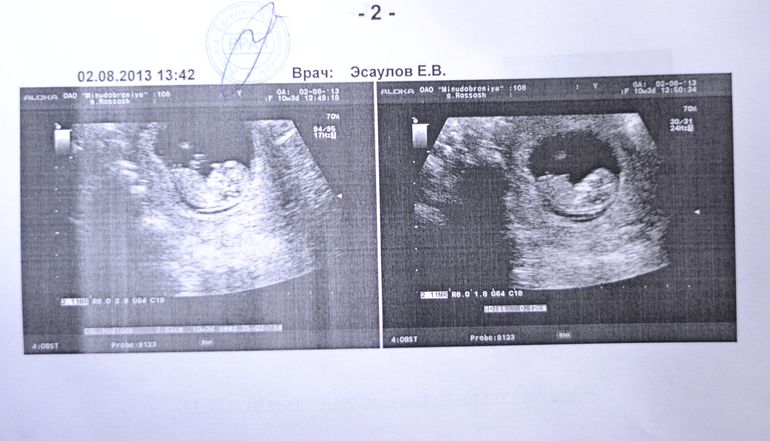

Срок был точно как в ББ, 10 недель и 3 дня))

В общем у нас будет один ребеночек,а я так надеялась на двойню,ну ничего)) Главное чтобы здоровенький был)) Пол,что и логично пока еще не понять,да там еще мало что понять))) Сердечко послушала-довольна))))

В полости матки визуализируется один живой плод в головном предлежании

Копчико-теменной размер плода 36.3мм-10 нед. 3 дня

Частота сердечных сокращений плода 160 ударов в минуту

Толщина воротникового пространства 1.2 мм

Преимущественная локализация хориона передняя стенка

Структура хориона не изменена

Особенности придатков матки в правом яичнике желтое тело 18*10мм(сказал попить дюфастон,но я предпочитаю утрик да его и пила все равно)

Ну и фото